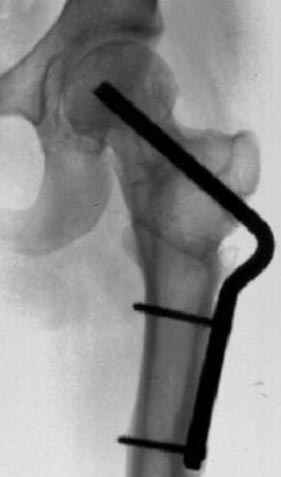

Несколько снимков из моей коллекции, чтобы разьяснить, почему мы до сих пор делаем различные варианты остеотомии.

N3 рисунок окончательный снимок, после операции моя рентгенограмма должен выглядеть примерно как эта картина. На N4 снимке клин перед удалением; N5 послеоперации 3 нед.; N6 окончательная рентгенограмма.

варус при проксимальном отделе 95 градусной пластиной.